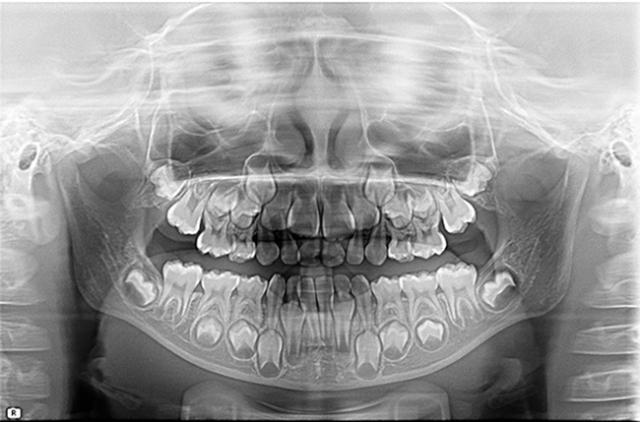

出生时:20颗乳牙的牙冠几乎全部形成并钙化,16颗恒牙牙胚形成恒牙